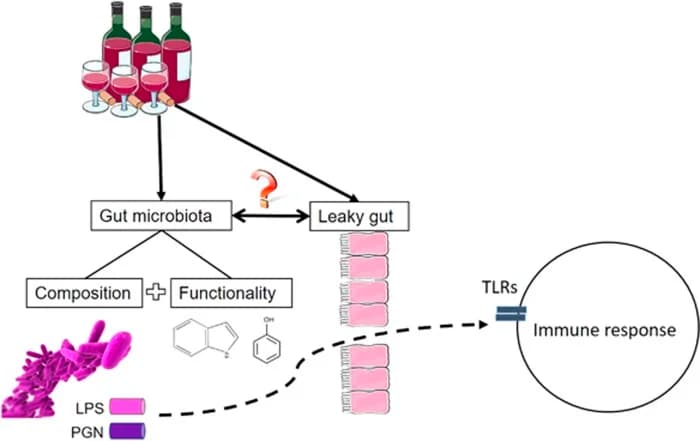

7. Protects Against Certain Poisons

The gut has 100x more MT receptors than the blood. R

It has 10-100x more melatonin than the blood. R

It also has 400x more melatonin than the brain. R

Gut melatonin is highest during the day, inversely from brain concentration levels. R

Melatonin in the gut reacts to food. R

Melatonin increases gastrin. R R

Melatonin reduced pain during sleep with patients that have IBS (irritable bowel syndrome). R R

When used alone or with omeprezole, melatonin helped GERD (gastro-esophageal reflux disease). R

In animal studies:

- Melatonin is able to increase Bacteroidetes and reduce the ratio of Firmicutes to Bacteroidetes. R

- It also increases Akkermansia, which is good for weight loss. R

- Alistipes, Anaerotruncus and Helicobacter marmotae were all reduced after melatonin treatment. R

- Melatonin reduces severity of colitis.R

- It reduces creation of ulcers in the stomach and severity of ulcers from ethanol. R R

- Ethanal-weekend-guts were strengthened from supplementation of melatonin. R

- It protected the gut from stress. R

- It improved the gut lining. R

- With malaria, it prevented liver cell death. R